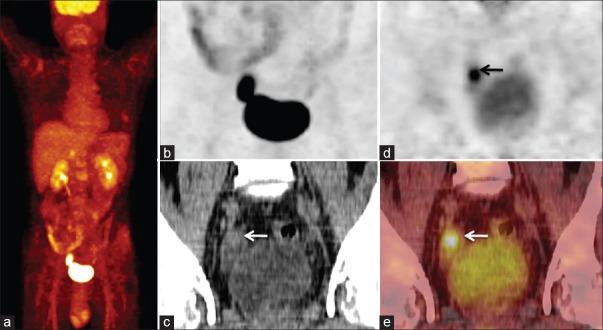

Urinary bladder diverticular carcinomas are uncommon with a lesser incidence of 0.8-10% and its diagnosis still remains a challenge. Cystoscopy is the most reliable method, but evaluating diverticulum with narrow orifices is difficult. Before the initiation of appropriate treatment, proper detection of bladder diverticular carcinoma and its locoregional and distant sites of involvement is necessary. Here, we present a case of 48-year-old male with urinary bladder diverticular carcinoma detected by forced diuretic (18)F-fluorodeoxyglucose positron emission tomography/computerized tomography ((18)F-FDG PET/CT). This case also highlights the significance of forced diuretic (18)F-FDG PET/CT in the detection, staging, and response evaluation of bladder diverticular carcinoma.

膀胱憩室癌并不常见,发病率较低,为0.8%-10%,其诊断仍然是一项挑战。膀胱镜检查是最可靠的方法,但评估开口狭窄的憩室很困难。在开始适当治疗之前,正确检测膀胱憩室癌及其局部和远处受累部位是必要的。在此,我们报告一例48岁男性膀胱憩室癌患者,通过强制利尿(18)F-氟脱氧葡萄糖正电子发射断层扫描/计算机断层扫描((18)F-FDG PET/CT)检测到。该病例还突出了强制利尿(18)F-FDG PET/CT在膀胱憩室癌检测、分期及疗效评估中的重要性。